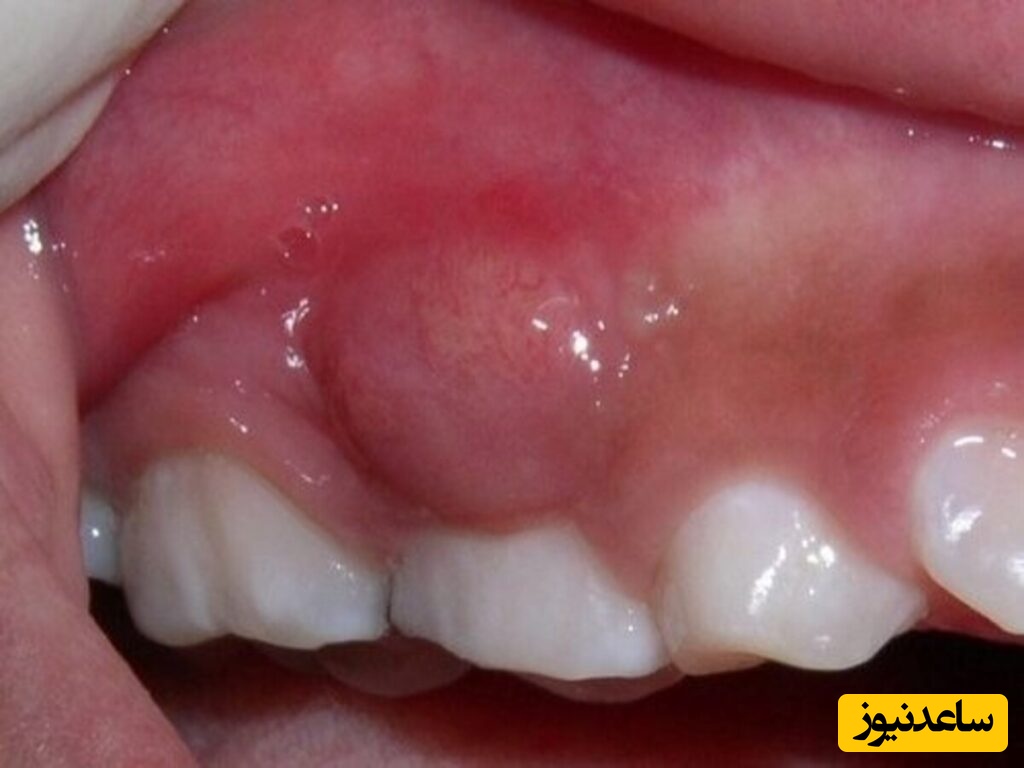

عفونت های دندانی می توانند عوامل مختلفی مانند ترک عمیق دندان، کرم خوردگی یا شکستگی دندان داشته باشند، عفونت های بسیار شدید ریشه دندان باعث ایجاد آبسه دردناک در دندان می شود، معمولاً آبسه های دندانی زمانی رخ می دهند که عفونت در ریشه دندان تا حد بسیاری افزایش یافته باشد، این مشکل یعنی عفونت در آبسه دندان به شکل ورم در لثه و صورت فرد ظاهر می شود.